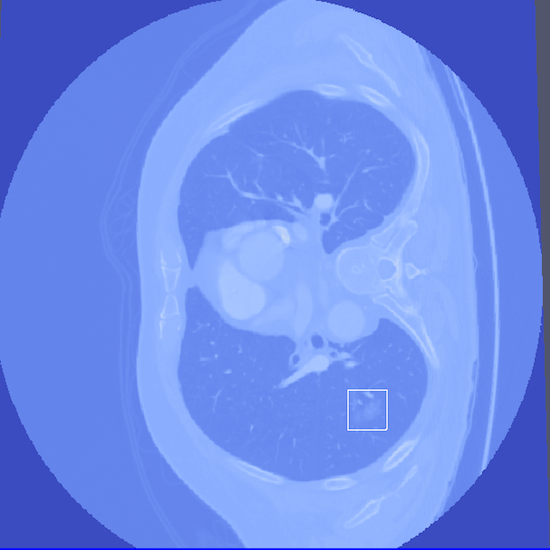

- Abstract: An exploration of whether conventional detection methods of lung cancers in low dose spiral CT scan could be improved using curvature features. In general, a large source of inaccuracy in detection rates can be attributed to irrelevant anatomical structures such as blood vessels. Often these irrelevant anatomical structures have different shape characteristics from lung nodules. For example lung nodules tend to appear bloblike as oppose to blood vessels, which appear cylindrical, or organ walls, which appear planelike. These curvature features were determined using eigenanalysis of the local second order image Hessian of each voxel, where the principal values are indicative of the local shape and provide more information than analysis performed on first derivatives alone.

- Method Overview: In each CT scan, the internal 3D lung volume was isolated using standard thresholding of pressurevalues ranges associated with lung parenchyma. The remaining voxels were conjoined using a connected components method, implemented through a union-find method, with small and isolated components removed. The remaining gaps were filled in using a standard 3D image closure method. First and second order partial derivatives were computed using Deriche filters, chosen for their stability and suitability in medical image scans. Then, for each of the voxels in the internal volume of the lung the local second order Image Hessian was generated and analyzed for preferred directions using eigenanalysis. This information was then used to weight the contribution of each voxel to standard lung nodule detection methods, to determine if giving stronger weight to voxels with local blob-like shape improved detections results.

Bottom Row: Examples of lung nodule detections.